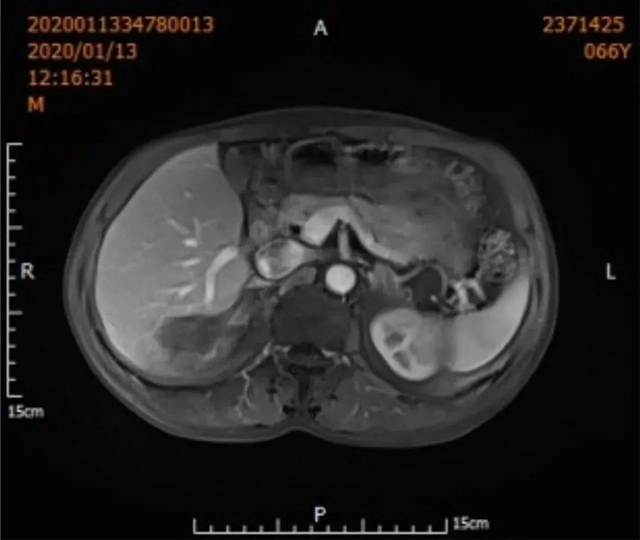

2019年12月3日,66岁的吴先生因“两对半异常10余年,发现肝占位1天”到西南医科大学附属中医医院就诊。

肝胆病科副主任王晓栋副教授接诊后为其完善相关检查后,结果提示:甲胎蛋白17.18ng/ml;腹部CT:肝硬化,肝右后叶低密度影;腹部MR:肝硬化,肝右叶后下段结节灶,考虑肝癌可能性大。

综合吴先生的病史资料,临床诊断为肝癌,根据影像学表现,王晓栋副教授建议吴先生可行手术切除或微创消融治疗,吴先生及家属考虑到年龄、糖尿病等因素,最终决定行“经皮肝脏肿物冷冻消融术”。

定期复查非常重要,早发现,早治疗,术后1月左右复查肝脏肿瘤标志物、肝脏增强核磁共振或CT、肝功能等。

病情稳定后通常情况下每隔2~3月复查肿瘤标志物、彩超、增强MRI或CT。